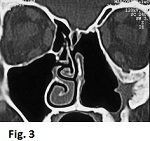

Tale metodica strumentale consente di valutare con cura l’erosione ossea circostante e l’eventuale estensione intracranica o intraorbitaria. La RMN permette di distinguere il tumore dalla concomitante presenza di secreto mucoso o mucopurulento e di effettuare la diagnosi differenziale con il polipo antro-coanale che è benigno. L’asportazione chirurgica completa rappresenta il trattamento ideale di tale patologia. Sia che si utilizzi una tecnica chirurgica più invasiva come la rinotomia laterale, sia che si utilizzi una tecnica chirurgica poco invasiva, come l’approccio endoscopico, è di fondamentale importanza eseguire una dissezione subperiostea e fresare l’osso sottostante: ciò consente di ridurre notevolmente le recidive. Presso il nostro Centro, l’approccio endonasale endoscopico viene impiegato nei tumori che interessano l’etmoide, lo sfenoide e la parete mediale del mascellare. Se il tumore si estende verso la parete laterale del mascellare tale approccio viene combinato con un approccio trans-mascellare mediante un’incisione sublabiale o si impiega direttamente il midface degloving (vedi il capitolo sull’angiofibroma del rinofaringe) utilizzando il microscopio per la rimozione del tumore (Fig.3).